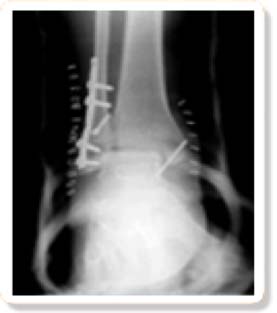

on site x rayX-rays are widely used in podiatry to diagnose the cause of pain, stiffness, and other symptoms, as well as to manage the treatment of fractures, arthritis and many other types of diseases and injuries that affect the bones and joints. Even though x-rays cannot provide clear images of soft tissues, they can still provide important information about some types of soft tissue injuries, helping to ensure treatment is as successful as possible. X-rays are also used prior to surgery to plan the best approach and are also used following surgery to monitor recovery.

X-rays may be performed while the patient is sitting or lying down, depending on the image that is being obtained. During the x-ray exam, the foot and ankle will be carefully positioned, and special cushions or bolsters may be used to keep them in that position while the x-ray is being taken. The lens of the x-ray machine will be placed close to the area of the ankle or foot that is being evaluated, and the x-ray will be clicked on and off. It takes just a moment to capture each image. Usually, more than one x-ray is taken to provide views from different angles. While the images are being taken, the technician will move to another area of the room but will still be able to see the room and the patient.